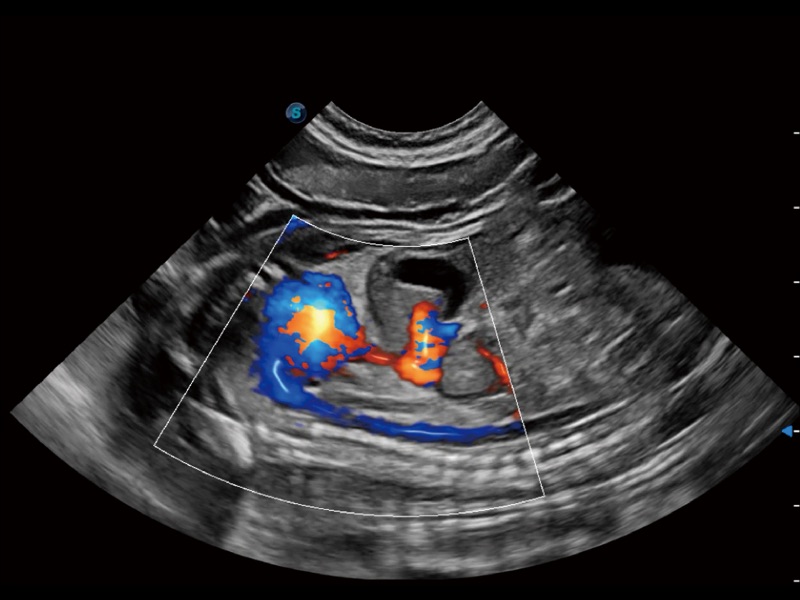

(犬)髂动脉血流

(犬)肾脏显微血流